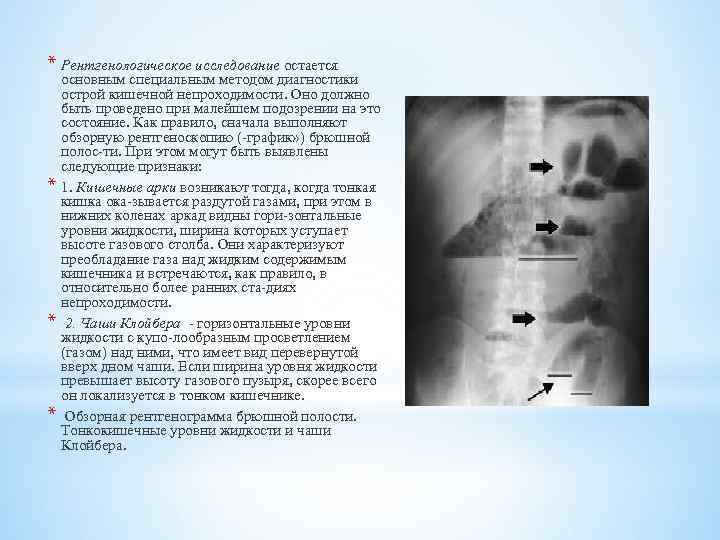

Иллюстрации и информация о симптомах острого кишечного непроходимости